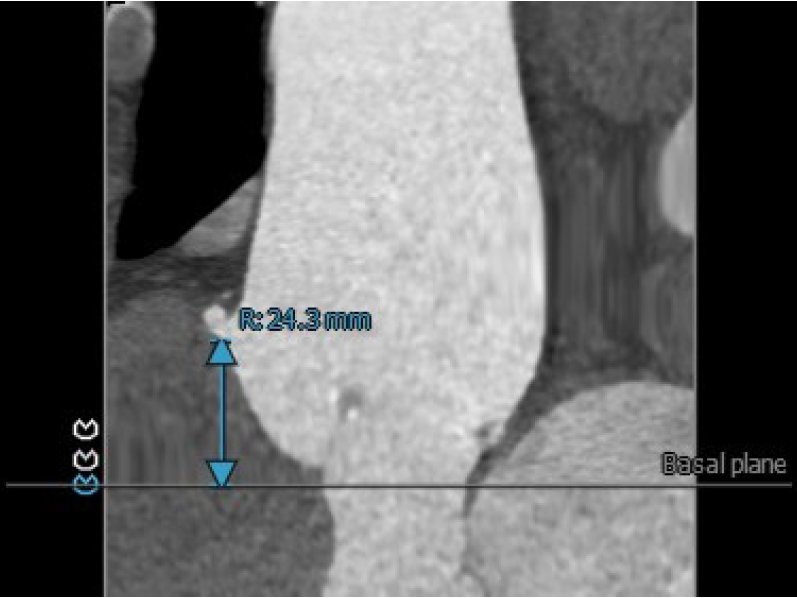

3.患者双侧冠脉开口高度可LCA:12.1mm,RCA:24.3mm。

右冠脉开口高度:24.3mm